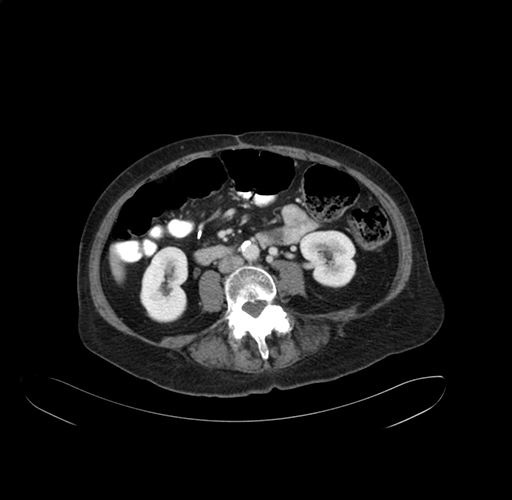

Pre-Chemo: Axial Venous